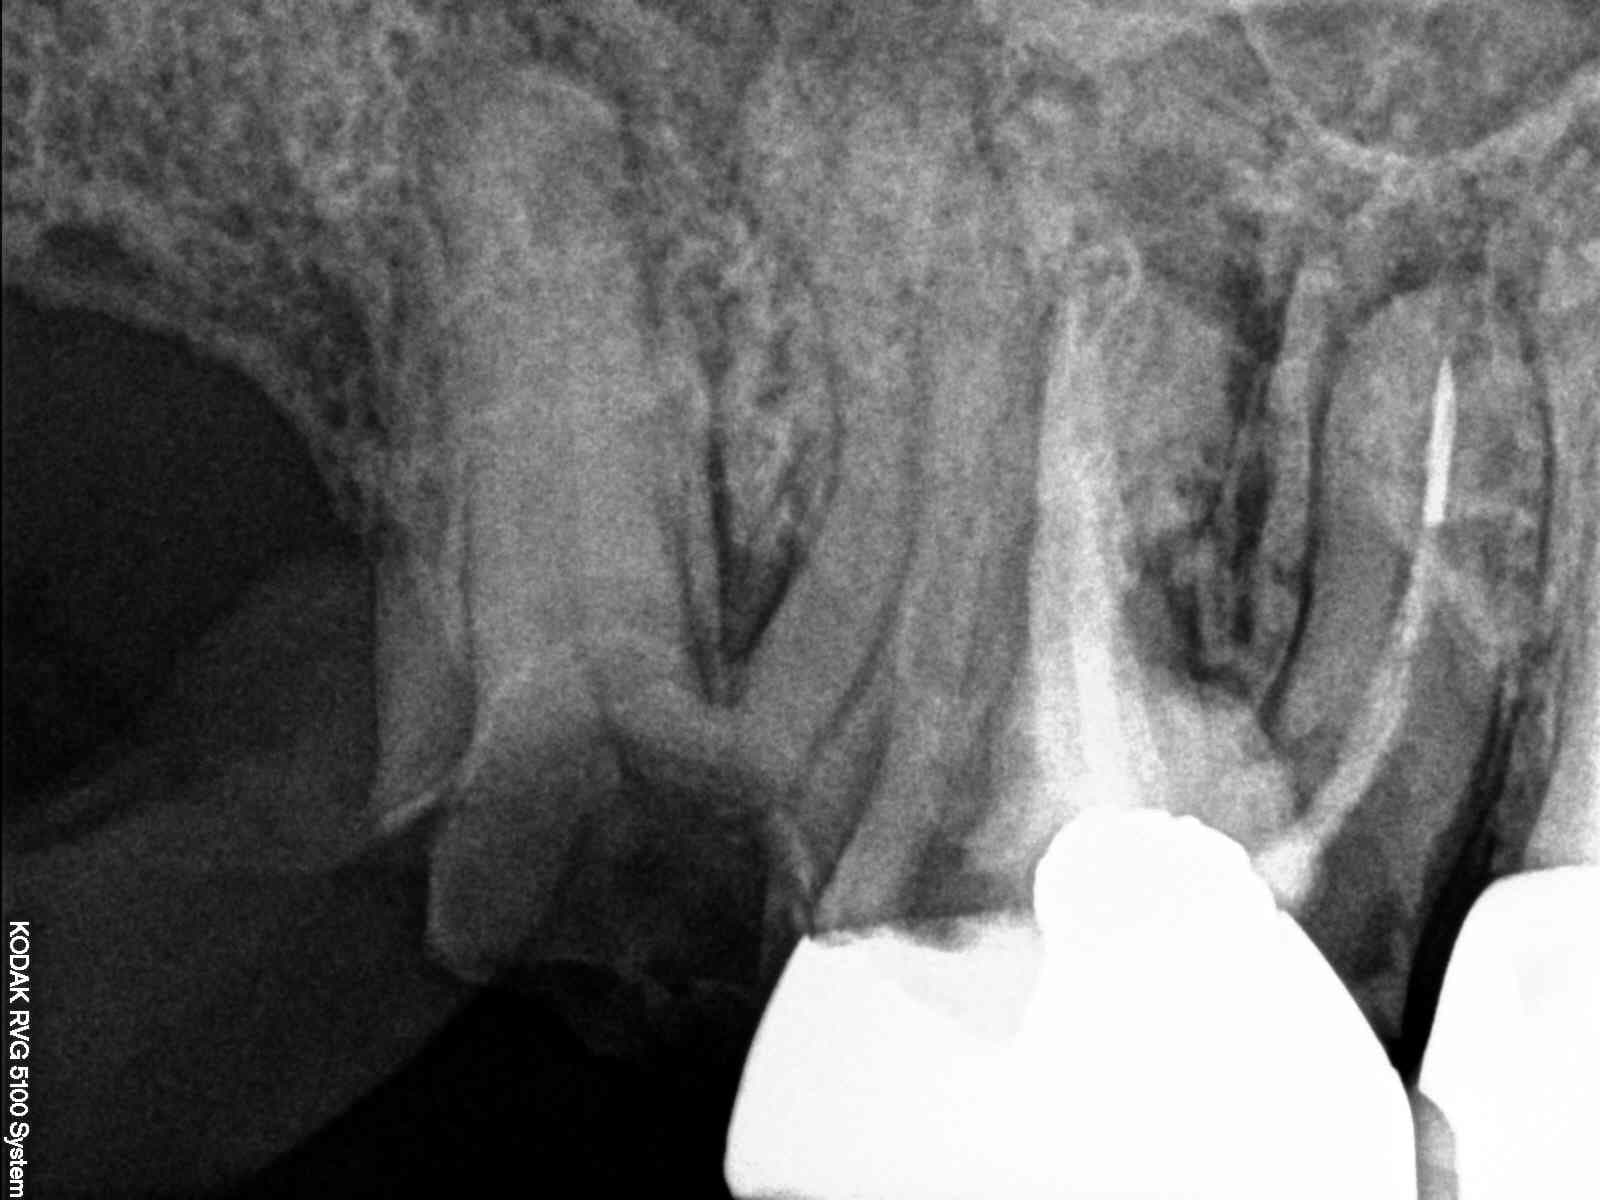

X ray 03 medium zvq18j - Eugenol